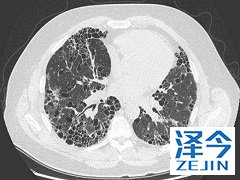

2015年1月,尼达尼布在欧盟范围内获批,用于肺纤维化的治疗。但是,为什么同一种药物能够治疗两种截然不同的疾病呢?这归因于尼达尼布的分子作用。在分子水平上,癌症和纤维化的差异性要比表面上看起来小得多。肺纤维化的起源与癌症的起源有着相似性。特发性肺纤维化是一种极为罕见的疾病。

那尼达尼布(nintednib)治疗特发性肺纤维化效果怎么样呢?尼达尼布可帮助IPF患者减缓肺功能下降从而延缓疾病进程、减少急性加重的风险,是IPF治疗领域的重中之重。同时减少因急性加重而就医及住院的次数,也可减轻家庭和社会的经济负担。尼达尼布是全球首个治疗特发性肺纤维化的创新靶向药物。

尼达尼布对于治疗特发性肺纤维化不是偶然的,这种疾病与肺癌的起源有相似性,所以治疗特发性纤维化能够有效也是意料之内的。特发性肺纤维化是一种少见的疾病,在临床上治疗这一疾病的药品很少,这为患者的治疗提供了方法,缓解了患者的疾病进程。